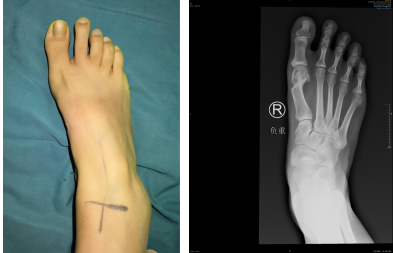

徐明亮主任了解了李女士的情况后,通过检查发现右足踇趾外翻增大,跖骨间受到挤压,所以走路时会产生疼痛。现在医院进行的第四代微创拇外翻矫正手术,除了微创外,进行三维畸形矫正,更好保护组织,更有利于术后早期恢复。

第二天徐明亮主任、周祥国医生团队为李女士进行了“右足拇外翻畸内固定术”。术中松解第1跖趾关节外侧关节囊、跖趾关节韧带,切除增生的拇囊,清理增生骨赘,纠正外翻畸形,行内固定。手术顺利,仅用时60分钟。

术前

术后